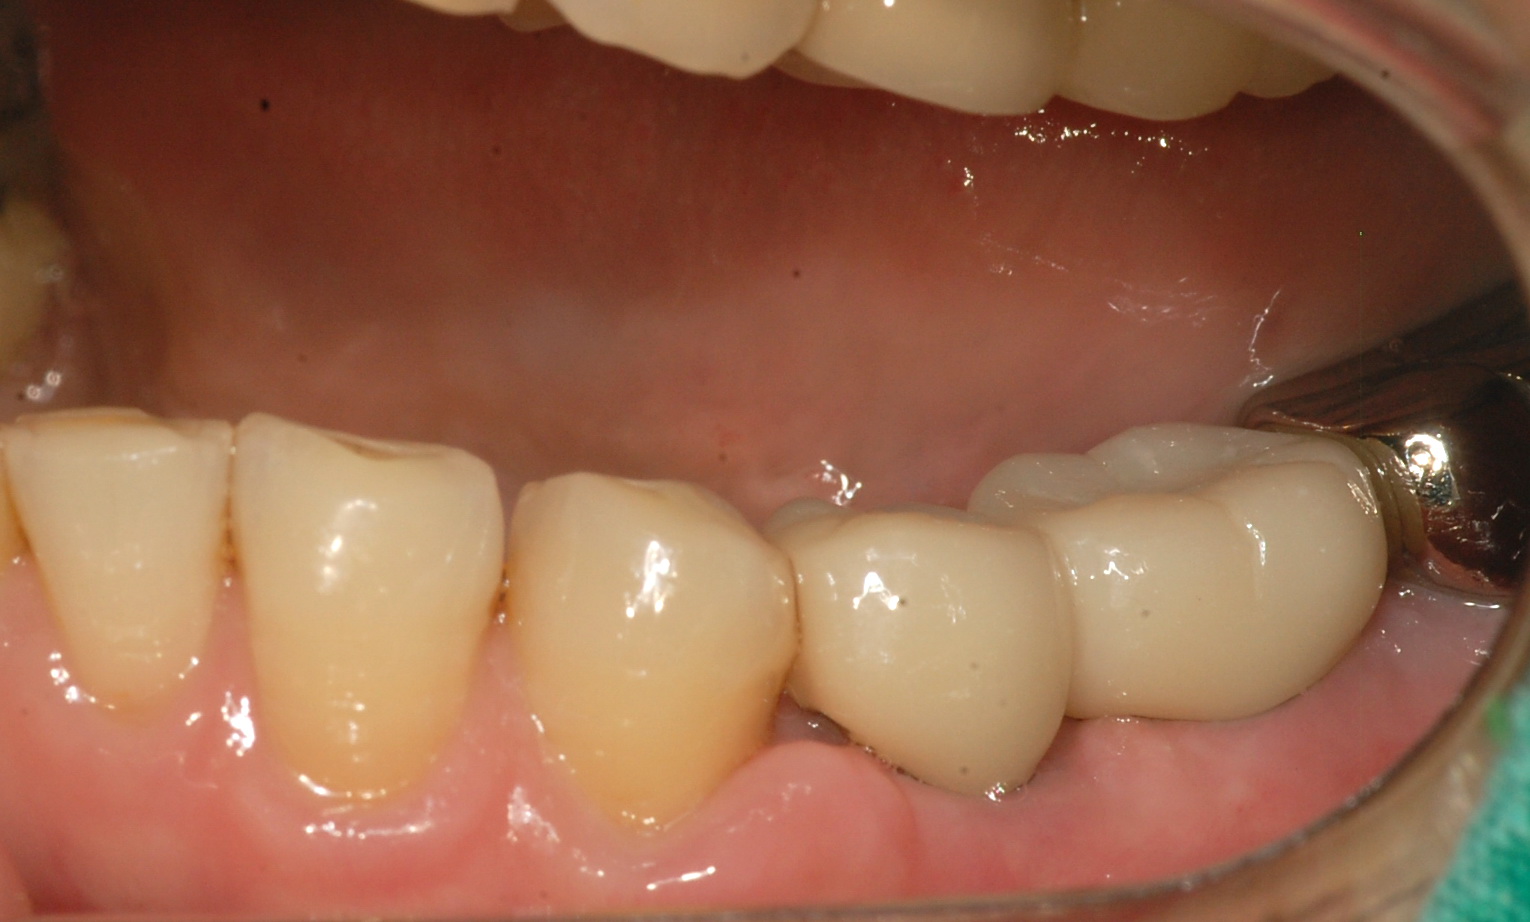

[임플란트] 제목 : 임플란트 지르코니아.

임플란트 지르코니아 보철